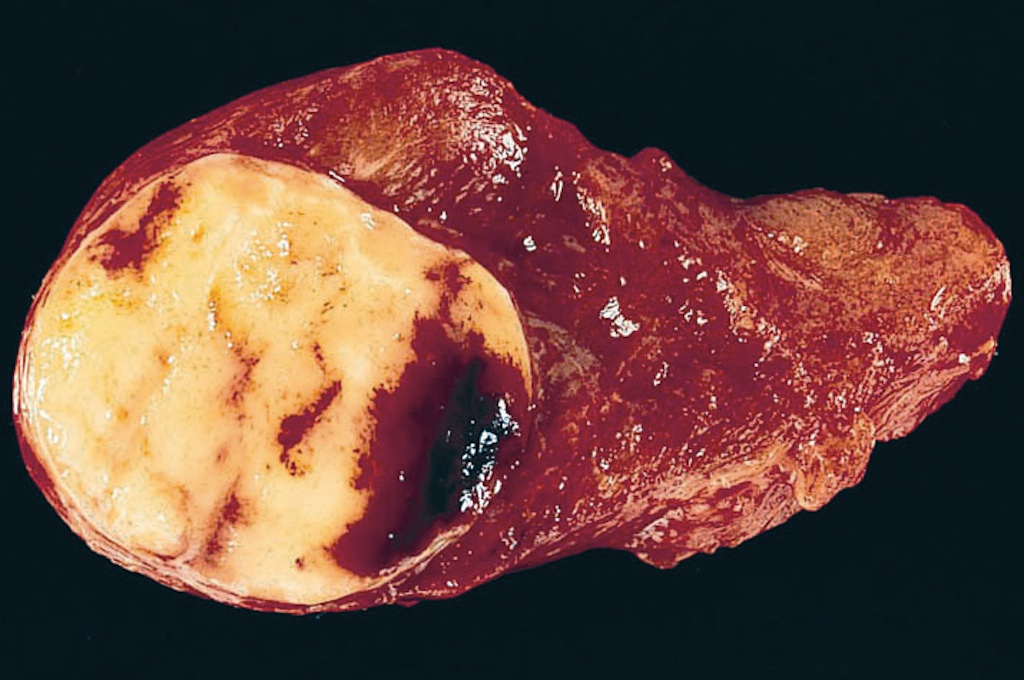

Gross description

- Solitary, encapsulated nodule; multiple if familial

- Variable size (1 - 10 cm)

- Solid, gray-white, tan to light brown

- Secondary changes: hemorrhage, cystic change, fibrosis, calcification, infarction; may develop post-fine needle aspiration cytology

- Rarely black; especially seen with minocycline therapy

Gross images

Contributed by Andrey Bychkov, M.D., Ph.D., Mark R. Wick, M.D. and AFIP

Images hosted on other servers: